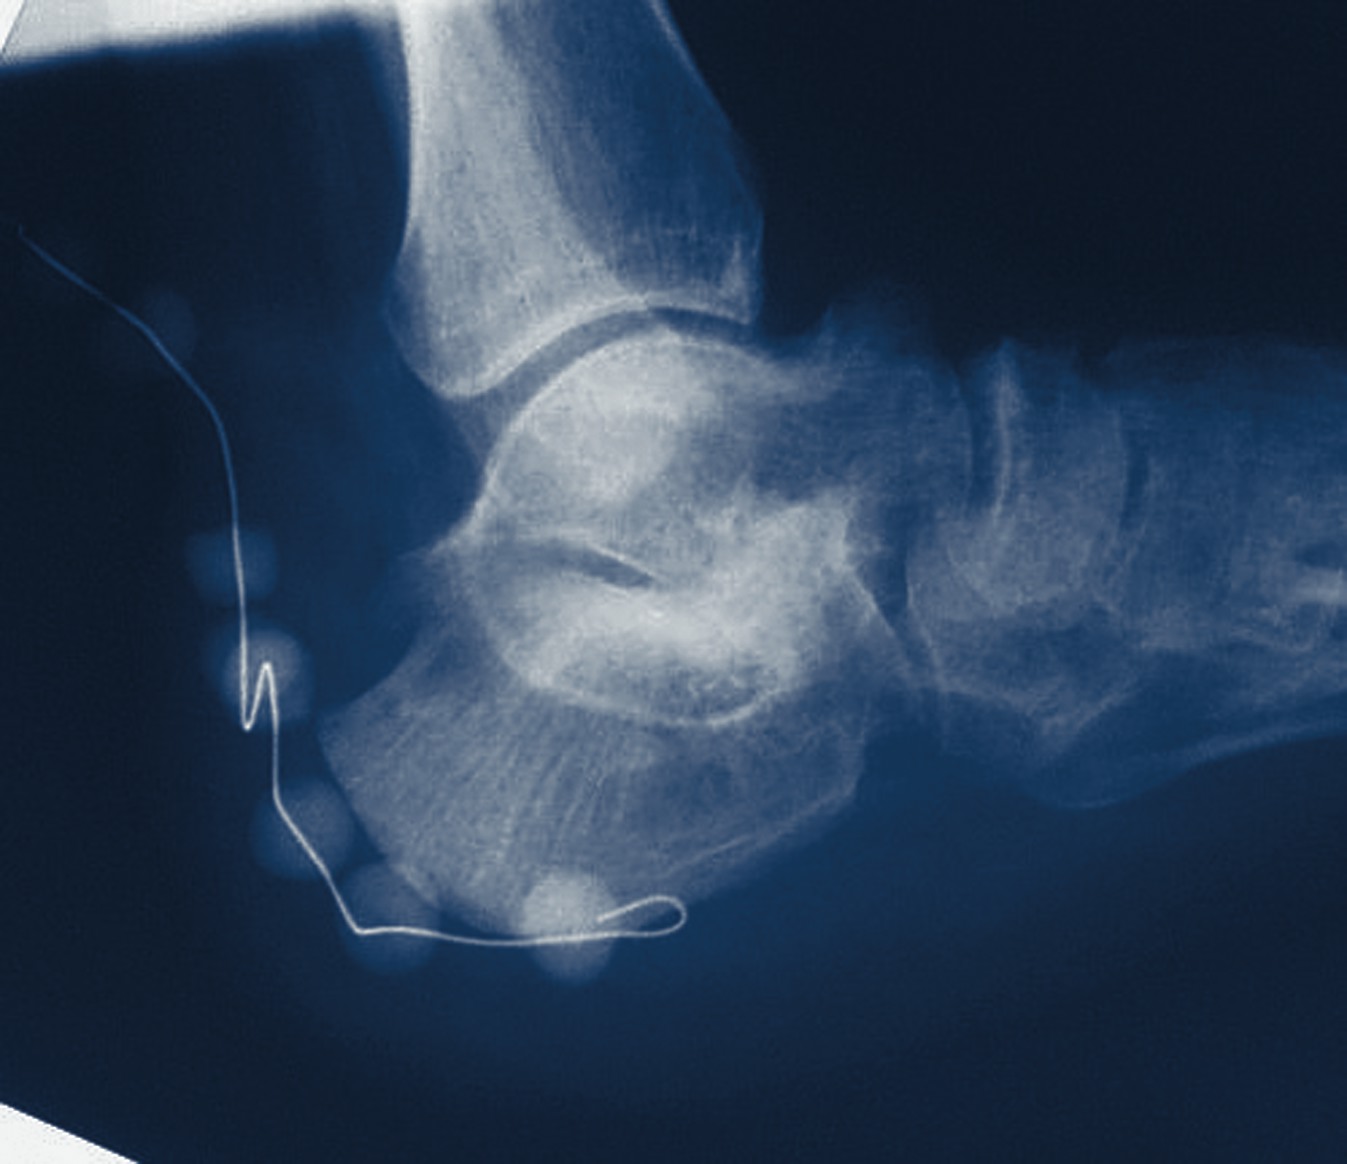

In addition to the over-prescribing of antibiotics, excessive use of prophylactic antibiotics for surgery is also an issue. Antibiotic prophylaxis accounts for approximately 30 percent of all antibiotics administered on surgical services in the United States.1 Prophylaxis is defined as the use of antibiotics to prevent infection. The objectives of prophylactic antibiotic use include preventing naturally occurring organisms from proliferating in a sterile surgical site, preventing organisms from producing disease and preventing infection by exogenous organisms.1 There are numerous advantages of using prophylactic antibiotics. These advantages include preventing potential infection in high-risk surgical procedures, protecting immunocompromised patients and preventing foreign implant colonization. However, Williams and Gustillo noted the possible risks of indiscriminate use of preventive antibiotics for orthopedic surgery. These risks included unnecessary expense, drug-related side effects and the potential to influence local and hospital microflora.2 The main concern with the indiscriminate use of prophylactic antibiotics is the emergence of resistant bacteria, including postoperative MRSA infections from clean surgical procedures. Considering that the incidence of infection in clean orthopedic surgery without antibiotic prophylaxis is 0.5 percent to 6.5 percent, it is unrealistic to think that prophylaxis is necessary in every case. Joseph, et. al., and Leaper agree that clean surgical procedures without the implantation of a prosthesis in patients with normal defenses do not necessarily justify routine use of prophylactic antibiotics.3,4 When are prophylactic antibiotics indicated? According to Joseph and Kosinski, antibiotic prophylaxis is indicated for foreign device implantation, trauma surgery, prolonged operative time and immunocompromised patients.3 Researchers have shown that implantating any foreign body impairs wound healing as well as the local immune response and defense mechanisms.5 Most of the literature in this area is based upon total hip and total knee prosthetic implants and is extrapolated to apply to the use of metal hardware implants in podiatric surgery. Based on the orthopedic literature, Joseph and Kosinski state that although the risk of developing an infection of a prosthetic implant is low, infection is catastrophic when it does occur. Therefore, they recommend using prophylactic antibiotics when performing clean, elective surgical procedures with an implant.3 In most traumatic injuries, the high occurrence of infection accounts for the primary cause of many complications including non-unions and instability following the injury.6 In trauma cases, researchers have shown that one should give antibiotics within three to six hours after inoculation in order to reduce the incidence of infection. Studies have shown a lower rate of postoperative osteomyelitis and infection when surgeons have used prophylactic antibiotics in trauma patients. Therefore, prophylactic antibiotics are considered an essential part of traumatic injury management.3 Patients undergoing surgical procedures with a prolonged operative time are at increased risk for infection. Since most intraoperative contamination can be traced to airborne organisms from the patient or operating room personnel, Joseph and Kosinski recommend prophylaxis for surgical procedures lasting more than two to three hours.3 Bowler, et. al., recommend restricting acute wound prophylaxis to a single dose of antibiotics at the beginning of the operation with an additional dose if operative time exceeds three to four hours. The objective is to achieve a high concentration of antibiotics at the time of incision and throughout the surgical procedure.8 Joseph and Kosinski state that one should consider antibiotic prophylaxis for immunocompromised patients, including patients with diabetes and the elderly.3 A conflicting view is presented by Zgonis, et. al., in their retrospective study of 555 patients. In this study, 55 percent of the patients received prophylactic antibiotics while 45 percent were not given any antibiotics.9 The antibiotic group had a 1.6 percent wound infection rate versus 1.4 percent for the group not given antibiotics. They noted the group that received antibiotics had more complex and longer surgical procedures, and there was more frequent use of internal and external fixation devices. In the study, researchers found that none of the examined factors, including age, gender, type of surgical procedure, operative time, tourniquet use, past medical history or use of internal fixation, were predictive of post-op wound infection or complication.9 Based upon these results, one could conclude that preoperative antibiotics are not indicated in clean podiatric surgical procedures. Cierny and Mader recommend antibiotic prophylaxis based upon the standard classification of surgical wounds.1 This classification system takes into account the surgical approach, immune system of the patient and risk of a postoperative infection. Clean wounds include elective surgery on non-compromised hosts under ideal operating room conditions. Since the overall incidence of wound infection is less than 5 percent, Cierny and Mader state that no antibiotic prophylaxis is indicated.1 Clean/contaminated wounds involve entering the oropharyngeal cavity, and the lumens of the respiratory, alimentary or genitourinary tracts. This category also includes clean surgery performed on immunocompromised hosts or surgery involving a break in sterile technique. Wound infections occur in approximately 10 percent of these procedures. Therefore, surgical prophylaxis is recommended for this category.1 Contaminated/dirty wounds include surgery performed through traumatic wounds, a major break in sterile technique and operating at the site of active infection. These procedures have infection rates ranging from 20 to 40 percent, necessitating the need for antibiotic prophylaxis and/or therapy.1